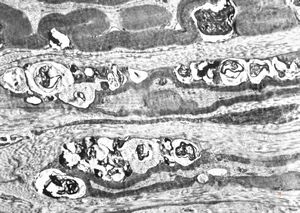

n. suralis - hypertrophic demyelinizing neuropathytoluidine-blue-stained semithin section

M, | hypertrophic (onion bulb) neuropathy accompanyingmultiple sclerosis

F,23y. | - n.suralis- hypertrophic demyelinizing neuropathy (onion bulbs)

F,23y. | - n.suralis- hypertrophic demyelinizing neuropathy (onion bulbs)

F,12y. | hypertrophic (onion bulb) neuropathy - n.suralis

F,12y. | hypertrophic (onion bulb) neuropathy - n.suralis

F,12y. | hypertrophic (onion bulb) neuropathy - n.suralis